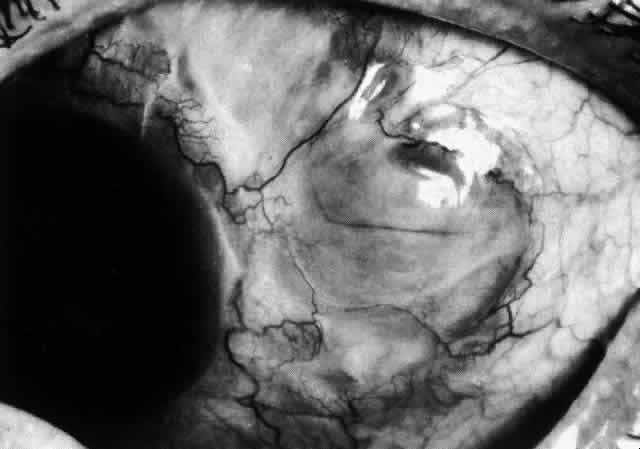

The sclera that is edematous is pushed forward, and the deep episcleral network is more congested than the superficial networks (Figs. 27 and 28). It is usually easy to ascertain by simple observation that the patient has scleritis and not episcleritis. However, it is not as easy to ascertain whether the patient has early necrotizing scleritis. It is in these patients that fluorescein angiography has considerable value, because the first changes are detectable in the ocular vasculature. Prompt and adequate treatment can prevent these changes from becoming irreversible.

Fig. 27. In scleritis, maximum congestion occurs in deep episcleral plexus, which is bowed forward by underlying scleral edema. Episcleral tissue is slightly infiltrated and superficial plexus is slightly congested (see Fig. 14). (Watson PG, Hayreh S, Awdry P: Episcleritis and scleritis. Br J Ophthalmol 52:278–279, 1968)

Fig. 28. Nodular scleritis. Both the anterior conjunctival slit and the deep scleral slit are displaced forward by the scleral edema. There is little separation between these two beams, indicating that all the edema is in the sclera and not in the overlying episclera. (Watson PG, Hayreh S, Awdry P: Episcleritis and scleritis. Br J Ophthalmol 52:278–279, 1968)